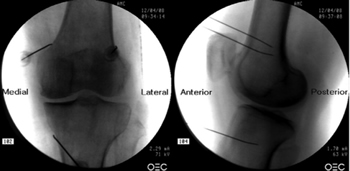

Fluoroscopy-guided genicular nerve radiofrequency

To perform a fluoroscopic-guided TRFGN, we need an anteroposterior (AP) and lateral view of the knee (Figure 2). First we place the patient in supine position with a pillow under the popliteal fossa (to make the patient more comfortable) (16). After performing asepsis and antisepsis of the knee, we proceed to locate the GN (Table II). SLGN is advancing the TFR needle toward the confluence of the lateral femoral diaphysis with the lateral femoral condyle in an AP view and at a mid-point of the femur in a lateral view. The SMGN is located by advancing the needle toward the confluence of the medial femoral diaphysis with the medial femoral condyle in an AP view and at a mid-point of the femur in a lateral view. Finally, the IMGN is located by advancing the needle toward the confluence of the medial tibial diaphysis with the tibial epicondyle in an AP view and at a midpoint of the tibia in a lateral view (16,17).

Fig. 2. Anteroposterior (AP) and lateral projection where therapeutic targets are observed using fluoroscopy. Image taken from Choi et al. (9). Reproduced with the permission of Jin Woo Shin.

Table II. Location of genicular nerves guided by fluoroscopy

Good AP and lateral view is very important. In AP projection, the tibiofemoral joint should have a similar width on both sides of the knee with the interspace open (9). In lateral projection, there must be a correct overlap of both femoral condyles to perform a satisfactory blockage of the SMGN and SLGN (18).

Most authors take the references described above to locate these nerves by fluoroscopy, except Fonkoué et al. (18), who find that the therapeutic targets of SMGN and SLGN (in a lateral view) are at the junction of the upper edge of their respective femoral condyles with the posterior cortex of the femur diaphysis, and not in half the thickness of the femur, as described classically (9,10,13).

Because the success of the TRF of the genicular nerves depends on the correct location of the RF needle tip (as close as possible to the nerve), Know et al. (17) demonstrated with magnetic resonance imaging that the points used classically in fluoroscopy for ablation of the three genicular nerves (SMGN, SLGN and IMGN) are correct. They observed that GN passes through the intersection formed by the diaphyseal and metaphysis line of the distal femur or proximal tibia (SLGN 92 %, SMGN 88 % and IMGN 100 %).